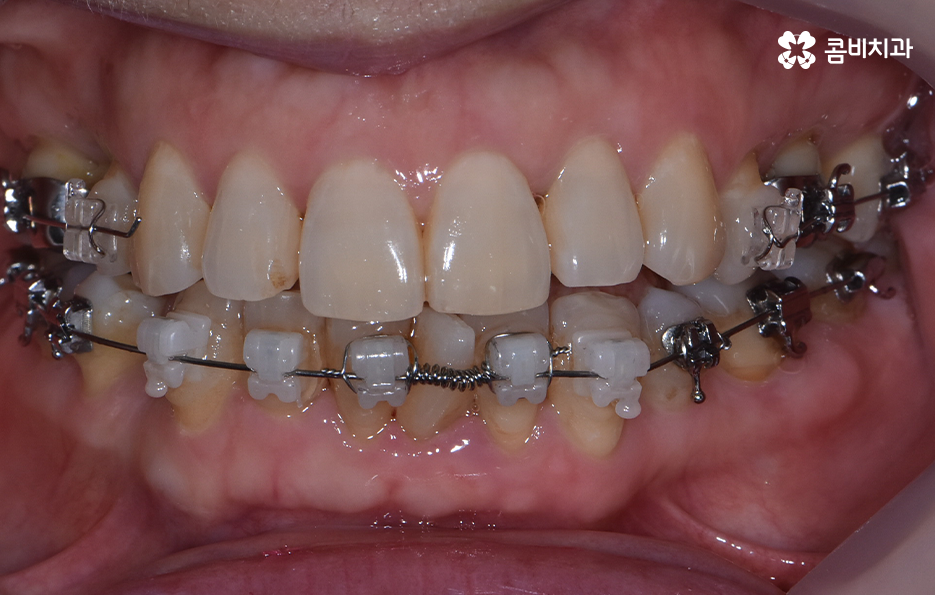

콤비교정은 윗니는 설측으로 진행하고 아랫니는 순측으로 교정기를 착용하기 때문에 웃을 때 주로 보이는 앞니는 교정기 착용이 티가 안난다는 점에서 크게 웃지 않는다면 교정기 착용이 거의 티가 안나는 수준으로 교정을 진행할 수 있어요